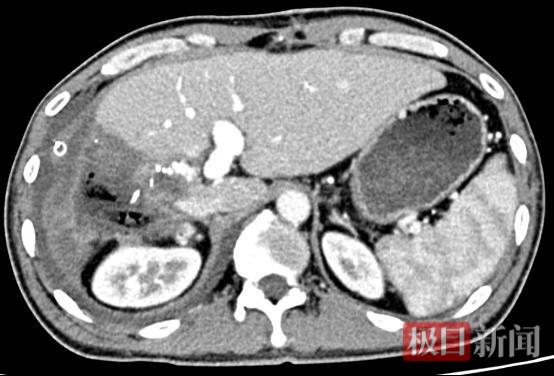

术后一月复查的CT影像

术后一个月复查显示,肝脏内未见病灶,肿瘤被清除,各项血液指标恢复正常。除体力稍弱外,黄先生已完全恢复正常生活。